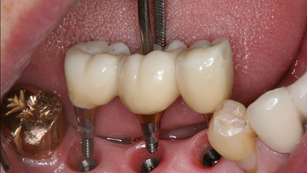

Implant placement with IS III active fixtures in the posterior mandible

Situation A 55-year-old male Hypertension A pre-operative panoramic radiograph revealed teeth missing on #45, #46 & #47. The treatment...